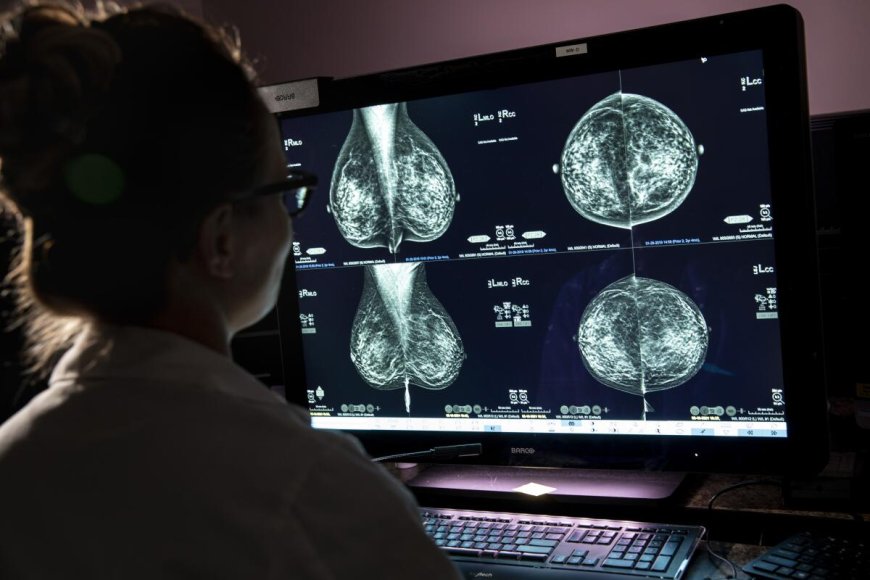

Las dos pruebas esenciales para una detección temprana del cáncer de mama son la mamografía y el eco mamario. El primer examen es capaz de detectar lesiones sospechosas y calcificaciones premalignas de menos a 0,5 cm, mientras que el segundo es especialmente útil para examinar mamas densas.

La doctora Maribel Yoris, radióloga del GMSP, recomienda la realización anual de la mamografía a partir de los 35 años, siempre acompañada de un eco mamario. En mujeres menores de 35 años y sin factores de riesgo, el eco mamario puede realizarse de forma individual. Si existen antecedentes familiares, los chequeos pueden comenzar antes de la edad recomendada.

El GMSP cuenta con equipos de alta excelencia para realizar ecografías mamarias y mamografías, con baja radiación y calibración de la presión según el espesor de cada mama para obtener imágenes precisas sin causar daño, indicó la radióloga Yoris. Además, realizan procedimientos de intervencionismo mamario, como el marcaje de lesiones antes de una cirugía. También analizan la pieza extirpada en el quirófano para confirmar que la lesión ha sido retirada por completo antes de que finalice la operación, lo que demuestra un alto nivel de precisión.

Este binomio de estudios es fundamental, pues la mamografía es reconocida como el método de elección para la detección temprana del cáncer de mama, capaz de identificar lesiones incipientes. A su vez, el eco mamario funge como un complemento esencial, aumentando la precisión diagnóstica, especialmente en mujeres con mamas de alta densidad.